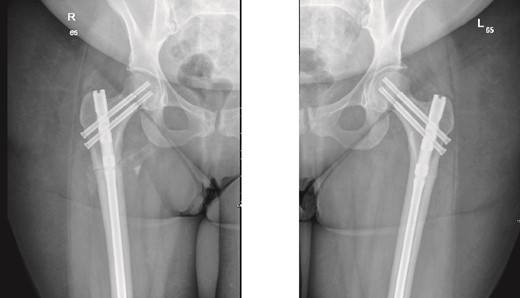

The left side was then prepped and draped. The same procedure was performed, with the nail size changed to 9 mm x 360 mm. Two proximal recon screws (90 mm) were inserted, followed by two distal screws. After fixation, the wound was irrigated, and closure was completed using Vicryl sutures for the subcutaneous tissue. The skin was closed with clips, and a sterile dressing was applied. The patient was extubated and transferred to her bed in stable condition, then moved to the post anesthesia care unit in stable condition. Immediate post-operative X-rays of both the right and left femurs are shown in Fig. 2.

Anteroposterior (AP) view of the right and left femurs after CRIF with IM nail.